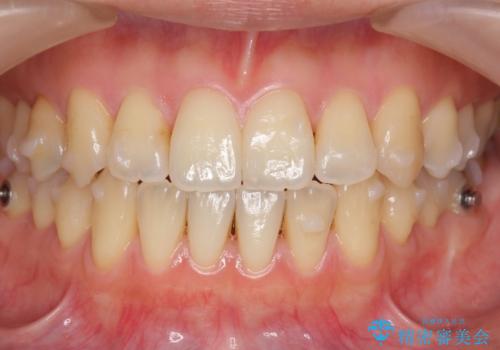

前歯のがたつき 若干受け口 インビザラインで

治療症例の内容

- 前歯のねじれおよび下の前歯が前に出ていることを気にして来院。

インビザラインで治療をおこないました。

前歯のねじれもなおり、比較的短期間でご満足いただけました。

部分矯正コースでしたので左下67の段差は特に治しておりません。

右下567及び左下6の虫歯治療も一緒に行っています。